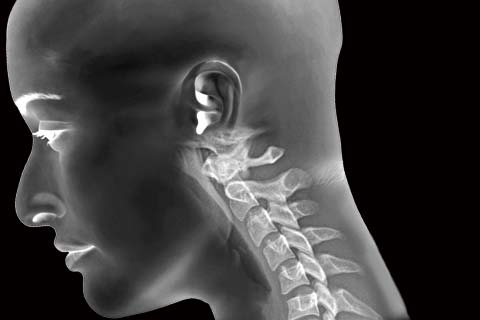

• 거북목증후군

잘못된 생활습관으로 목의 곡선이 일자로 또는 역C자 형태로 변형된 상태를 거북목 증후군이라 합니다.

거북목증후군 치료방법

• 비수술적 치료 물리치료, 약물치료, 주사치료, 운동치료(도수치료), 체외충격파, 신경성형술, 고주파수핵감압제거술

• 수술적 치료 현미경디스크제거술, 인공디스크치환술, 척추유합술